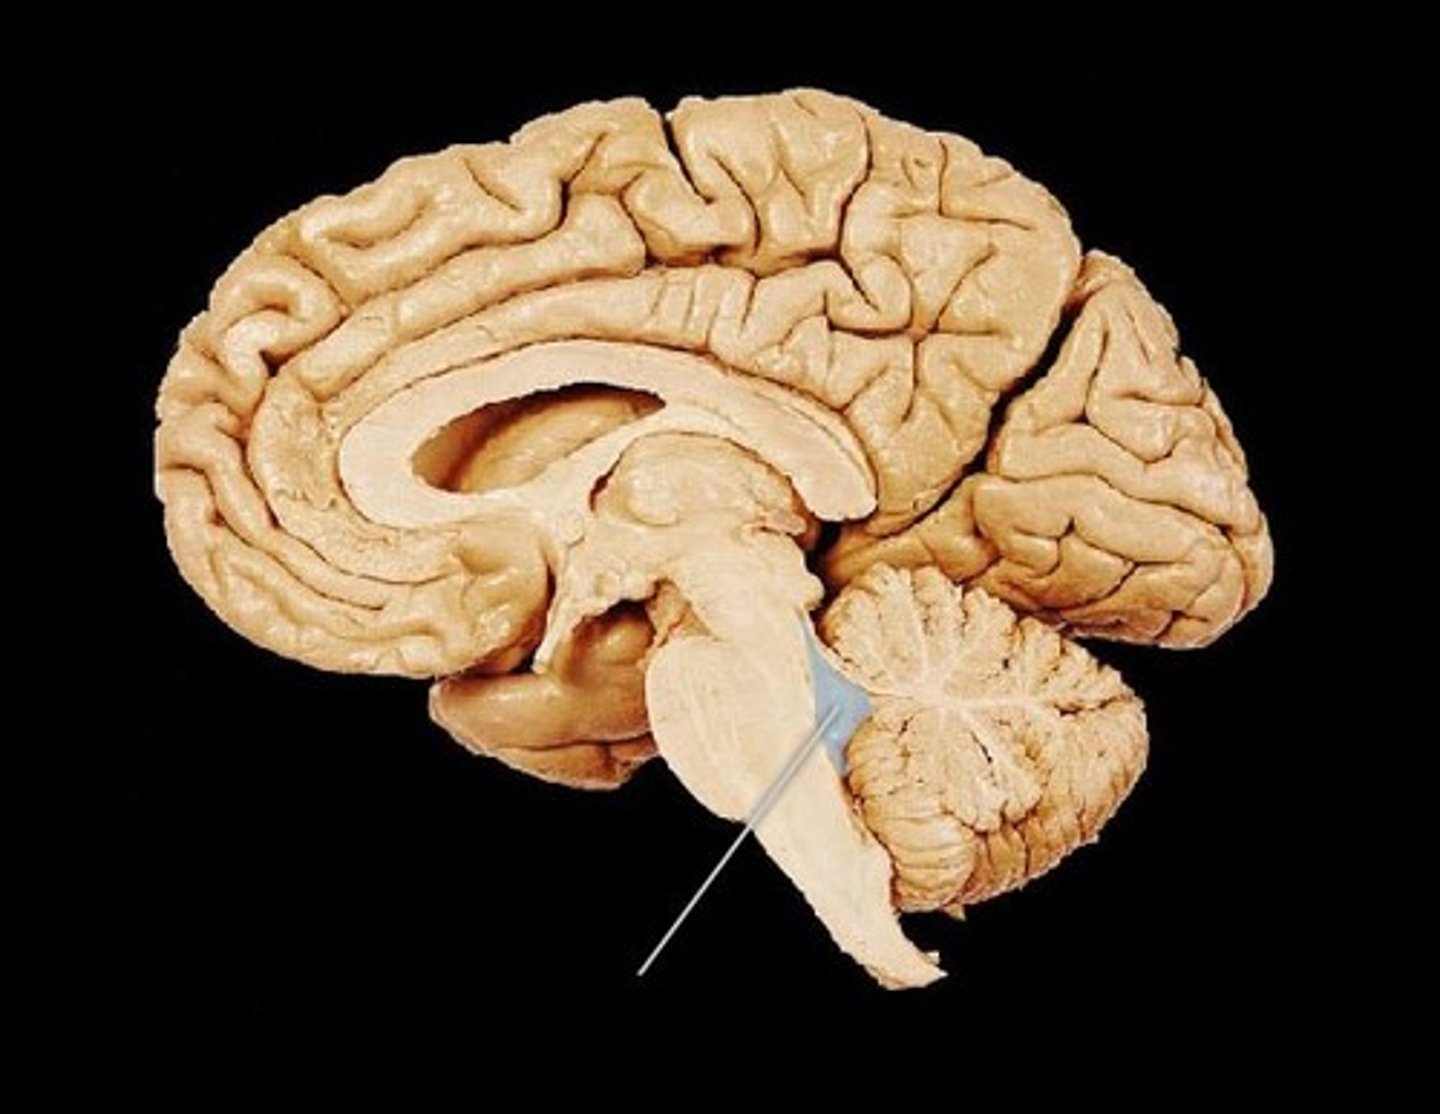

Cerebellum

"little brain" attach to the top of the brain stem. Components include vermis, arbor vitale, cortex, peduncles

Brain Stem

Continuation of spinal cord. Contains medulla oblongata, pons and midbrain

Midbrain

a small central part of the brainstem, developing from the middle of the primitive or embryonic brain.

Pons

bulging brain stem region between midbrain and medulla.

Medulla Oblongata

most inferior part of brain stem, eventually becomes spinal cord. Autonomic reflex center.

cerebral aqueduct

connects 3rd and 4th ventricle

fourth ventricle

runs through brain stem (midbrain) and becomes the central canal of the spinal cord.